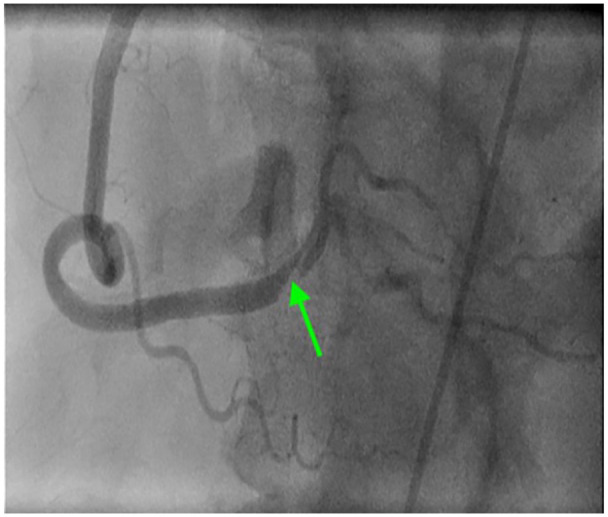

一名18岁的青少年患有明显的动脉粥样硬化性心血管疾病(ASCVD)危险因素,并发急性胸痛。他的心电图显示st段下位抬高。急诊冠状动脉造影显示右冠状动脉血栓性闭塞。他接受了罪魁祸首病变支架置入术,临床完全恢复,继发于心肌梗死的心电图异常也得到了解决。

An 18-year-old teenager with significant atherosclerotic cardiovascular disease (ASCVD) risk factors developed acute chest pain. His electrocardiogram showed inferior ST-segment elevations. Emergent coronary angiogram revealed complete thrombotic occlusion of the right coronary artery. He underwent stenting of the culprit lesion with complete clinical recovery and resolution of his electrocardiographic abnormalities secondary to myocardial infarction.